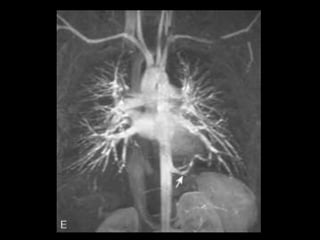

Embolia Pulmonar Patologiacomum e representa a terceira causa de morte nos EUA; Resulta de um trombo formado nos sistema venoso; Radiografia de tórax tem valor limitado: tem mais valor em excluir outras condições; Exame de escolha: angio-TC(MD); Acurácia da TCMD depende: do tamanho da artéria afetada e do tamanho do êmbolo;

• 62.

Embolia Pulmonar Diagnóstico deembolia aguda na TC com contraste é baseado na visualização direta de falhas de enchimento parciais ou completas dentro das artérias pulmonares; Sinal da “rosca”; Sinal do “trilho de trem”; Outro sinal útil: formação de ângulos agudos com a parede vascular, a perda completa da opacificação e o aumento do diâmetro do vaso acometido.

• 70.

Embolia Pulmonar Tromboscrônicos: com frequência aparecem como defeitos de enchimento em forma de crescente ou laminares aderidos às paredes da artéria pulmonar; Calcificações podem estar presentes; Armadilhas: tempo de delay, volume de contraste, sangue não opacificado oriundo da veia cava inferior e do átrio direito( interrupção transitória de contraste);